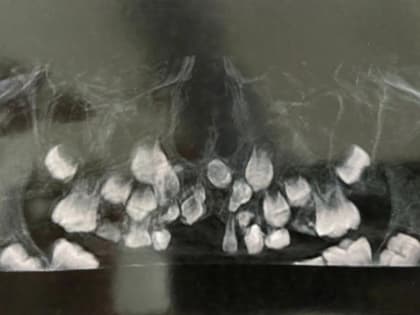

Врачи Ростова помогли ребенку, у которого восемь лет не росли зубы

Медики из областной детской клинической больницы помогли 8-летнему мальчику с редкой челюстной аномалией.